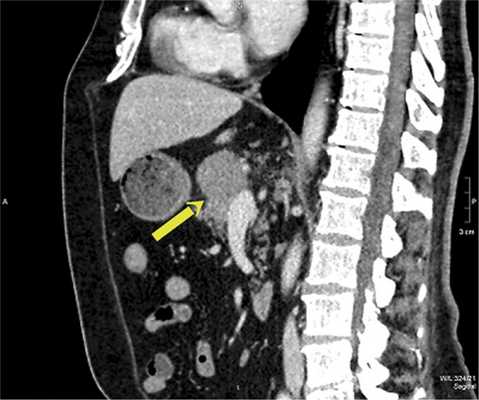

КТ органов брюшной полости с внутривенным контрастированием (23.05.2016): печень обычно расположена, краниокаудальный размер правой доли до 159 мм. В правой доле печени определяются единичные гиповаскулярные образования округлой формы, имеющие зону кистозной плотности в центральных отделах, в S7 до 24 мм в диаметре, на границе S7/6 деформирующее внешний контур печени образование размером до 44×32 мм, в S6 — до 30 мм. С нижней поверхностью S4, рядом с ямкой желчного пузыря, сливается образование, схожей структуры, расположенное преимущественно за пределами контура печени, округлой формы, размером до 27×12×20 мм, внутри- и внепеченочные желчные протоки не расширены. Желчный пузырь не увеличен, без рентгеноконтрастных включений. Селезенка не увеличена, структура однородная. В перешейке поджелудочной железы определяется гиповаскулярное образование с экзофитным ростом, неправильной округлой формы, размерами до 30×32×35 мм. Образование контактирует с поверхностью хвостатой доли печени, прилежит к сосудам портального бассейна в области конфлюэнса, а также по поверхности образование огибают общая печеночная артерия, гастродуоденальная артерия и собственная печеночная артерия, кровоснабжающая левую долю печени (правая доля печени кровоснабжается собственной печеночной артерией, идущей от верхней брыжеечной артерии). Остальные отделы поджелудочной железы с признаками атрофии. Вирсунгов проток не расширен. Прилежащая передняя парапанкреатическая клетчатка рядом с перешейком железы тяжистая, в ней определяются единичные лимфатические узлы размером до 6 мм. Надпочечники типичной Y-образной формы, правый надпочечник без объемных образований, в латеральной ножке левого надпочечника определяется образование размерами 12×11 мм, плотностью при нативном исследовании до 22 HU, накапливающее контрастный препарат в артериальную фазу до 97 HU и сбрасывающее его к отсроченной фазе до 48 HU. Почки обычно расположены, кортикомедуллярная дифференцировка сохранена. В синусах обеих почек определяются парапельвикальные кисты размерами: справа — до 32×16 мм, слева — до 25×17 мм. В нижнем сегменте левой почки также определяется киста размером до 39×32 мм. Чашечно-лоханочная система не расширена, выделительная функция синхронна, своевременна. Сосудистые ножки дифференцированы. В малом сальнике немногочисленные лимфатические узлы размером до 7 мм каждый, интрааортокавальные и по ходу почечных ножек справа размерами до 14 мм, в печеночно-двенадцатиперстной связке узлы максимальным размером до 28×16 мм. Выпота в брюшной полости нет. Атеросклеротические изменения аорты и подвздошных сосудов. Заключение (рис. 1, рис. 2):опухоль поджелудочной железы. Метастатическое поражение печени. Абдоминальная и забрюшинная лимфаденопатия. Образование в левом надпочечнике также вероятно метастатического характера. Кисты почек.

Рис. 1. КТ брюшной полости с внутривенным контрастированием. а — поперечный срез, стрелками указаны объемные образования поджелудочной железы и печени; б — поперечный срез, очаговые образования правой доли печени.

Рис. 2. КТ брюшной полости с внутривенным контрастированием (сагиттальный срез, стрелкой указано образование поджелудочной железы).